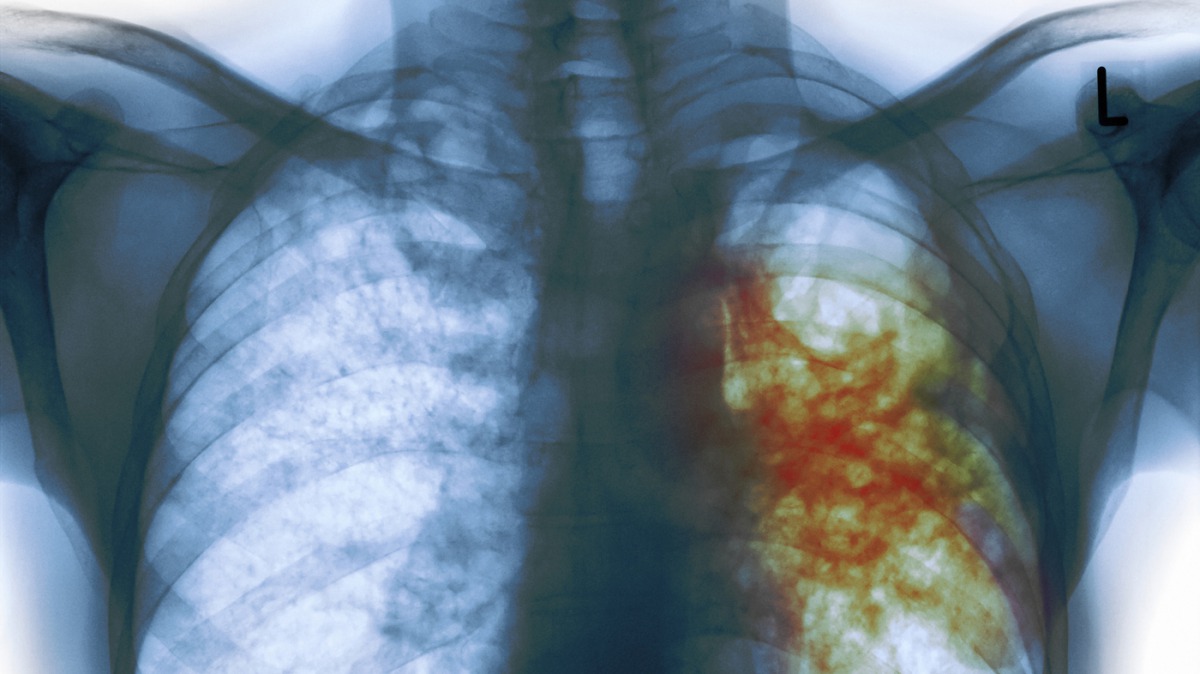

New Delhi: Millions of tuberculosis patients in India will receive daily treatment after the Supreme Court Monday ordered the government to change the current dosing practice amid activist claims it was endangering lives.

Around 2.5 million new cases of TB were reported in India in 2015, according to the World Health Organisation, the latest figures available for a country accounting for one in four global cases of the disease.

Around 200,000 people die in India every year from TB, according to various estimates.